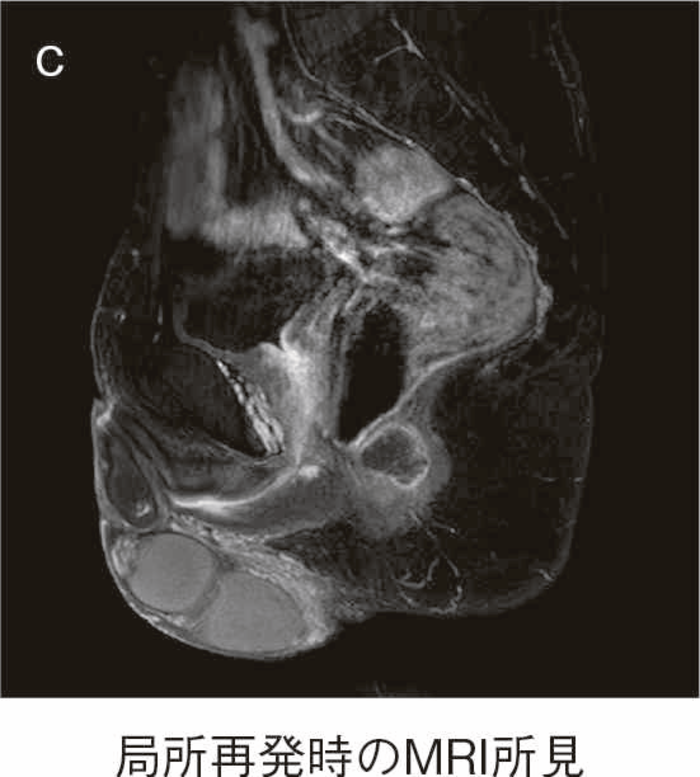

直腸粘膜をすべて切除し,回腸囊と肛門を手縫い吻合する。UCに対しても根治性が高い術式である。図14のように,肛門管粘膜の切除開始ラインは歯状線の肛門側で,肛門陰窩をすべて切除する。切除開始ラインが歯状線よりも口側になり,一部肛門管粘膜(移行帯上皮)を温存させた結果,この残存した粘膜からの発癌を強く示唆する症例報告も存在する2)。また,IAAを行ったにもかかわらず,術後に発癌したという症例報告も存在するが,多くは術後3年以内に発症している症例が多く,術前の直腸癌の局所再発が原因ではないかとの意見が一般的である3)。下部直腸から肛門管にかけて早期癌を合併するような症例では,術後の病理検査で,DM0,RM0であっても図15のように局所再発を生じる可能性もあるので,定期的な画像診断とともに,直腸診を行い,局所再発がないことを確認すべきである4)。

- 桑原隆一,池内浩基,楠 蔵人,他:直腸肛門管早期癌に対する大腸全摘回腸囊肛門吻合術後に吻合部再発を来した潰瘍性大腸炎の1例.日消外会誌2022;5:464-472